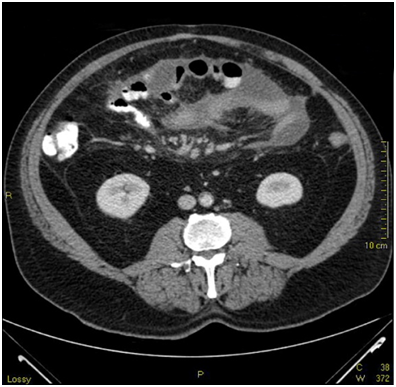

Admission labs showed a slight elevation in alkaline phosphatase, platelets and white blood cell count. There were no other major laboratory abnormalities and/or signs of infection. CT scan showed compartmentalized interloop hypodense fluid collection throughout the mesentery with associated fat stranding and small mesenteric nodules. (Images 1-3) There was encasement of small bowel loops, pleating of the mesentery and contraction of the peritoneal cavity. Mild small bowel dilatation without obstruction also noted.

CT scan is the main diagnostic tool with two distinct patterns on cross sectional images: (a) diffuse involvement of the peritoneal cavity and (b) focal intraperitoneal masses. Our patient presented with diffuse involvement of the peritoneal cavity without omental caking or masses. Small bowel encasement with interloop fluid and radial small bowel distribution was noted, as well as "stellate" mesentery due to tumoral infiltration. (Image 1,2,3) Differential diagnosis from imaging standpoint includes peritoneal infections such as tuberculosis, histoplasmosis and peritoneal carcinomatosis.6